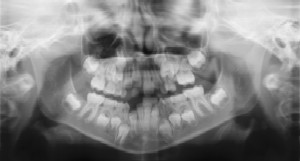

Dental Radiographs (X-Rays)

Radiographs (X-Rays) are a vital and necessary part of your child’s dental diagnostic process. Without them, certain dental conditions can and will be missed.

Radiographs detect much more than cavities. For example, radiographs may be needed to survey erupting teeth, diagnose bone diseases, evaluate the results of an injury, or plan orthodontic treatment. Radiographs allow dentists to diagnose and treat health conditions that cannot be detected during a clinical examination. If dental problems are found and treated early, dental care is more comfortable for your child and more affordable for you.

The American Academy of Pediatric Dentistry recommends radiographs and examinations every six months for children with a high risk of tooth decay. On average, most pediatric dentists request radiographs approximately once a year. Approximately every 3 years, it is a good idea to obtain a complete set of radiographs, either a panoramic and bitewings or periapicals and bitewings.

Pediatric dentists are particularly careful to minimize the exposure of their patients to radiation. With contemporary safeguards, the amount of radiation received in a dental X-ray examination is extremely small. The risk is negligible. In fact, the dental radiographs represent a far smaller risk than an undetected and untreated dental problem. Lead body aprons and shields will protect your child. Today’s equipment filters out unnecessary x-rays and restricts the x-ray beam to the area of interest. High-speed film and proper shielding assure that your child receives a minimal amount of radiation exposure.